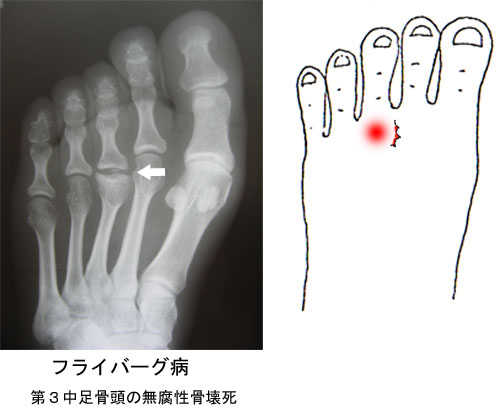

特に原因なく歩くと足のゆびの付け根に痛みが出る疾患です。レントゲン写真でみると、中足骨の骨頭の部分が幅広く平らに変形しています。第2中足骨次いで第3中足骨に多く、12歳から18歳の女性に多く発症します。

成長期に骨の成長する部分(骨端核)の血液の流れが悪くなり、部分的に成長が止まる骨端症の一つです。第2ケーラー病ともよばれます。第2中足骨に多く発症するのは、第2中足骨が最も長く、靴をはくことによって長軸上のストレスがかかりやすいためと思われます。